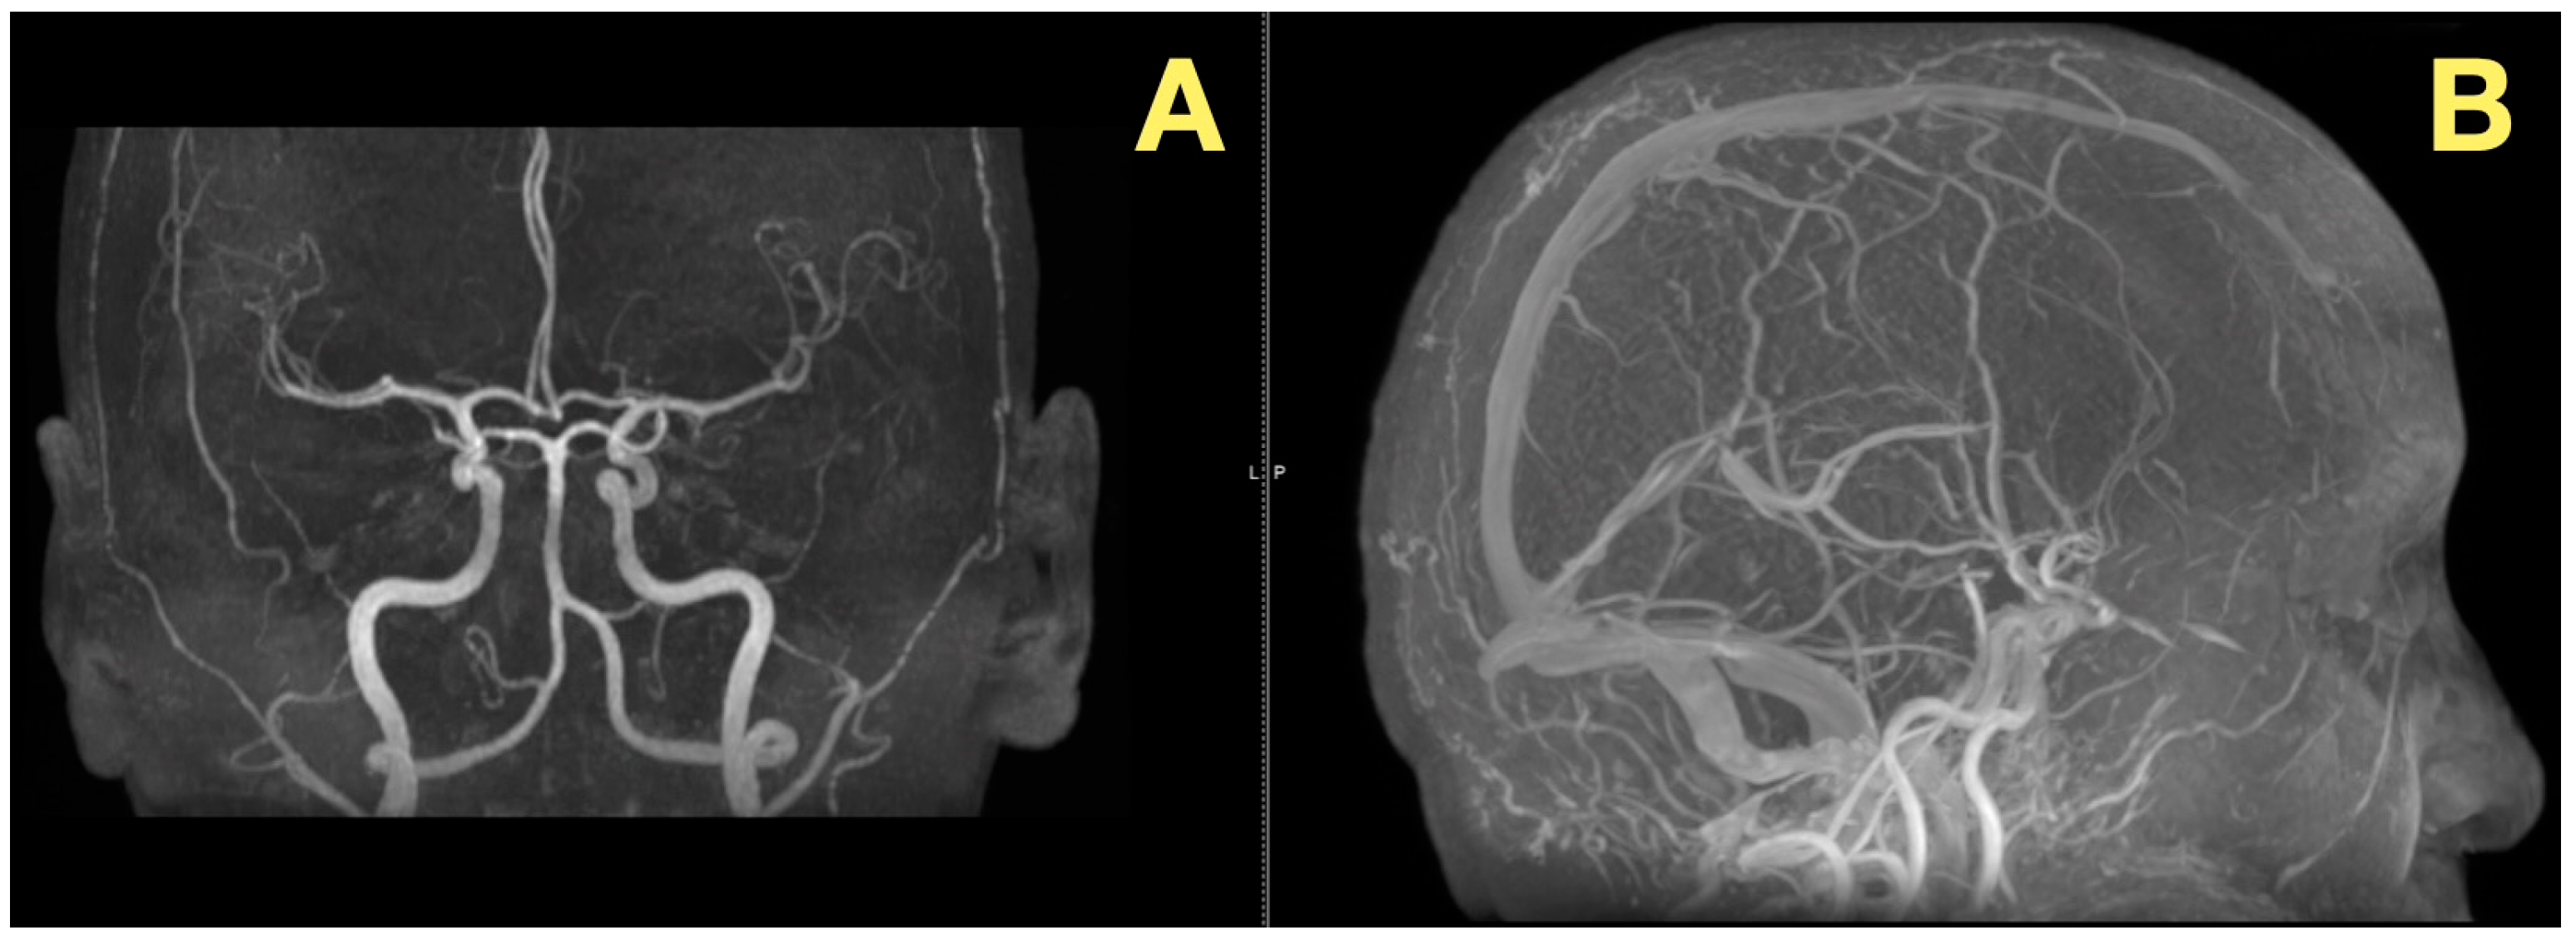

In addition to its rarity, the case also stood out due to the fact that all of the patient’s preoperative angiograms revealed a normal architecture of cerebral vasculature and no indication of aneurisms, arteriovenous malformations, or impaired venous outflow (Figure 2A,B). Further, the Circle of Willis was fully developed and symmetrically distributed, and the dural venous sinuses were unobstructed. As such, these studies ruled out vascular-related causes of intracranial hypertension and were consistent with a slowly expanding, avascular lesion.

Figure 2. Preoperative vascular imaging. (A): Frontal MRA maximum-intensity projection: normal configuration of the circle of Willis without aneurysm or stenosis (B): Lateral MRA: preserved arterial flow and patent dural venous sinuses, excluding vascular or venous causes of intracranial hypertension; the pressure increase is attributable to CSF-outflow obstruction by the fourth-ventricular mass.